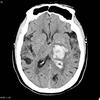

**IVH** - On CT imaging it appears as hyperdensity within the dark CSF spaces within the ventricles.

**Ring enhancing lesion** (T1 w/contrast) DDx - abscess, TB, neurocysticercosis, mets, glioblastoma, lymphoma, toxo

Left subdural with some midline shift

Subdural on CT head

Extradural on CT head

Subarachnoid haemorrhage on CT head

**Intraventricular haemorrhage**: hyperintense (bright) blood within the ventricles (with a fluid level); may be **primary**: started in ventricles or **secondary**: extension of extra-ventricular bleed (usually SAH or intracerebral e.g. basal ganglia)